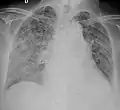

A case of miliary tuberculosis in an 82-year-old woman:

Testing for miliary tuberculosis is conducted in a similar manner as for other forms of tuberculosis, although a number of tests must be conducted on a patient to confirm diagnosis.[4] Tests include chest x-ray, sputum culture, bronchoscopy, open lung biopsy, head CT/MRI, blood cultures, fundoscopy, and electrocardiography.[10] The tuberculosis (TB) blood test, also called an Interferon Gamma Release Assay or IGRA, is a way to diagnose latent TB. A variety of neurological complications have been noted in miliary tuberculosis patients—tuberculous meningitis and cerebral tuberculomas being the most frequent. However, a majority of patients improve following antituberculous treatment. Rarely lymphangitic spread of lung cancer could mimic miliary pattern of tuberculosis on regular chest X-ray. [15]